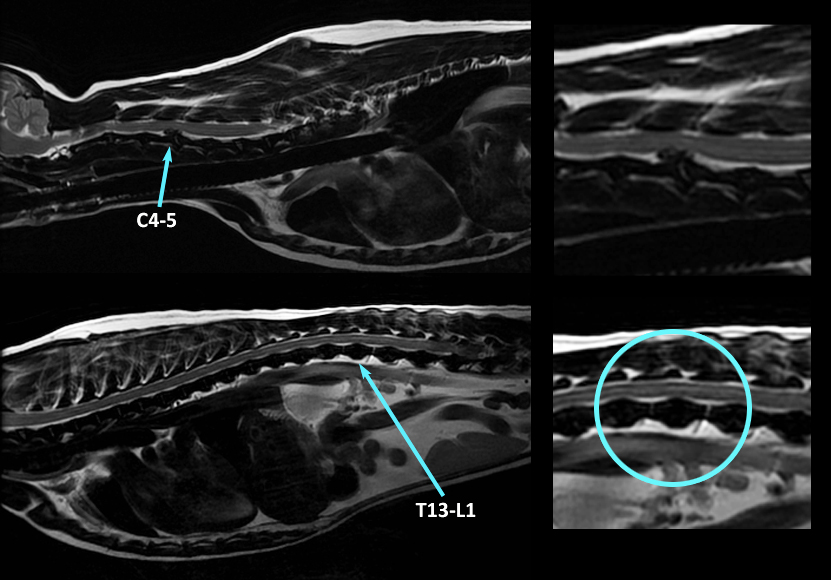

Il y a des chiens pour qui la m…alchance colle aux fesses… En voici un ! Ce petit chien a eu un diagnostic d’extrusion discale aiguë (Hansen type 1) il y a trois semaines par IRM (première image ci-bas), avant d’aller en chirurgie. Il a très bien récupéré, jusqu’à développer de nouveau des troubles neurologiques, cette fois localisés T3-L3. Bang !!!! Une nouvelle extrusion discale à T13-L1 (image du bas) ! C’est ce qui s’appelle des extrusions « back-à-back », ou « neck-à-back »… ;-(